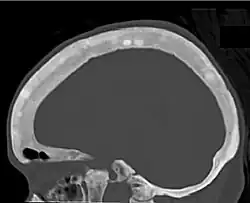

![CT shows focal areas of osteosclerosis.[18]](./_assets_/CT_of_sclerotic_lesions_in_the_skull_in_renal_osteodystrophy.jpg) CT shows focal areas of osteosclerosis.[18] CT shows focal areas of osteosclerosis.[18]